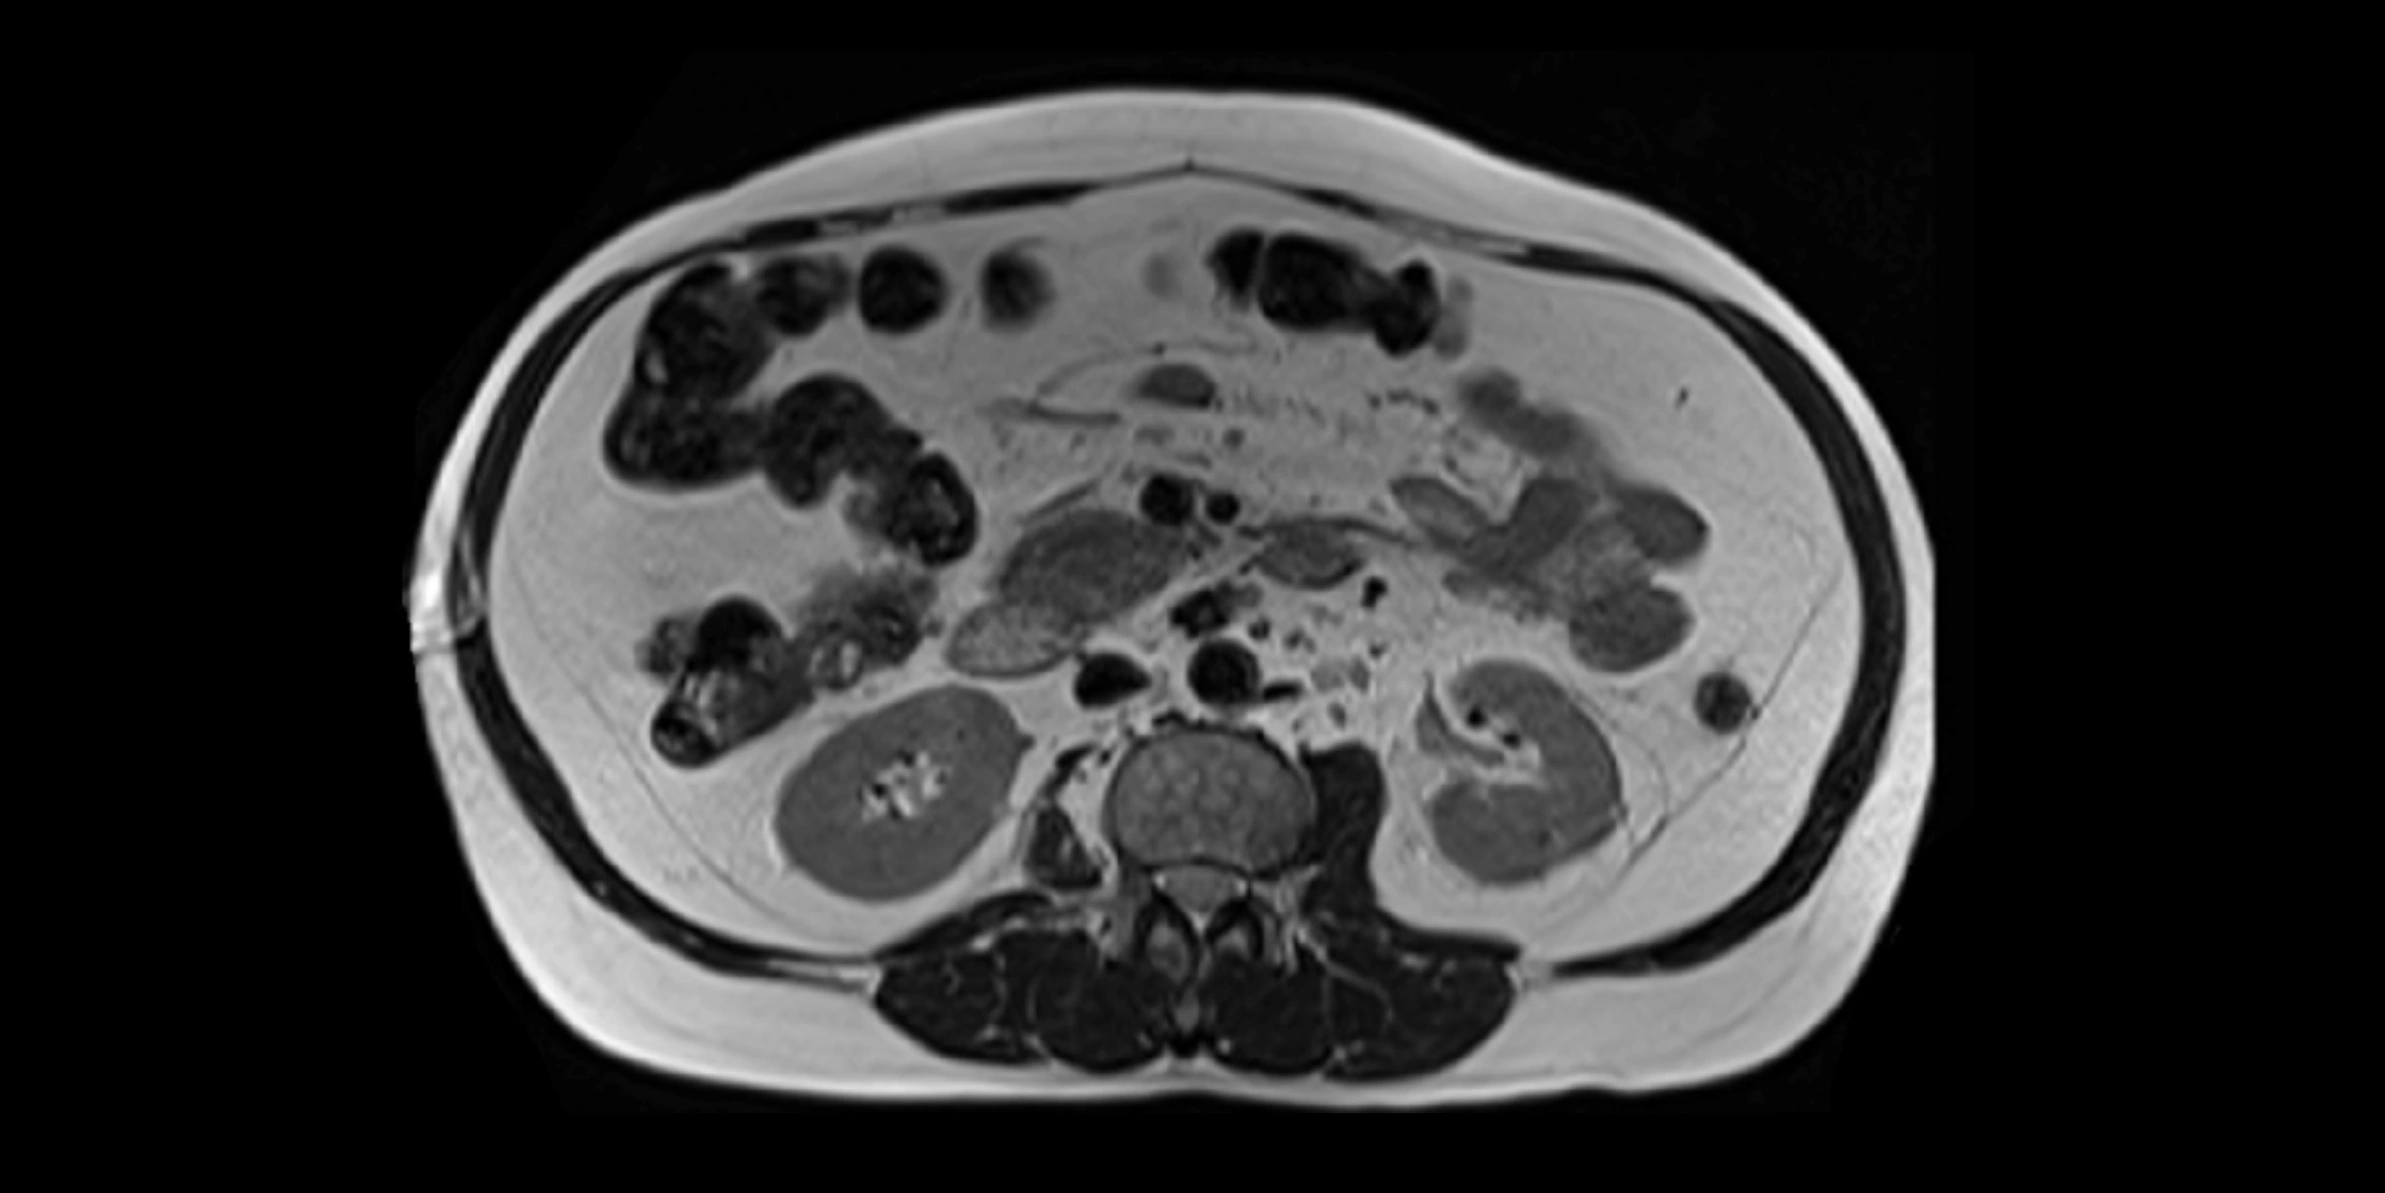

CT Appearance

CT Pre-Contrast:

• Caudate lobe appears as a soft-tissue density, isodense to the rest of the liver

• Enlargement may be appreciated in cirrhosis or Budd–Chiari syndrome